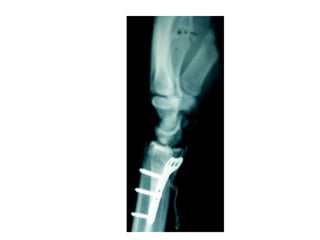

Tubular plates

 3.5 system - 1/3rd Tubular

 4.5 system - Semitubular

 Limited stability

 Collared hole

 Lateral malleolus

 Distal ulna / Olecranon

 Distal humerus